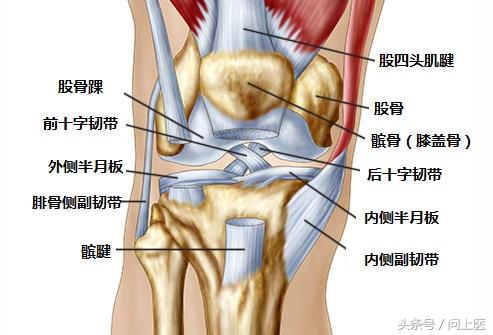

膝盖有很多运动部件,而且也经常被使用,所以出现问题的可能原因有很多。多次重复一种运动,尤其是如果没有循序渐进的过程,则可能会导致“过度使用”损伤。一些轻微的磨损和撕裂也会造成问题,尤其是年龄较大时。事故可能会导致骨折或组织撕裂,一些疾病也会使身体攻击自身关节。当膝关节出现问题时,及时就诊有助于医生诊断和治疗。

如果撞击或摔倒严重损伤了膝盖,则可能会导致受损部位的骨骼(股骨、胫骨或膝盖骨)断裂或脱位,需要立即就诊。有时,骨折发生得较为缓慢,因为它会造成股骨末端出现微小裂缝,所以当患者开始使用膝盖时,才会发展为骨折。

2. 十字韧带撕裂

这种情况通常发生在足球或篮球运动中,患者突然改变方向后就无法移动了,这可能是因为撕裂了膝盖后方的十字韧带。患者的膝盖会疼痛和肿胀,并感觉不稳定。

所有固定膝关节的组织都有可能被撕裂或拉伤,如连接骨骼与骨骼的韧带、连接骨骼与肌肉的肌腱。过度使用肌腱会导致肌腱炎。

8. 半月板撕裂

突然扭转或旋转时(尤其是膝盖承受全部重量时),就有可能会撕裂半月板(充当股骨和胫骨之间缓冲垫的弹性软骨)。前交叉韧带(ACL)的每一侧都有一个半月板。关节炎或年龄较大会提高半月板撕裂的风险。该疾病导致的疼痛定位不明确且难以描述,患者的膝盖可能会僵硬、肿胀、难以移动和伸展。